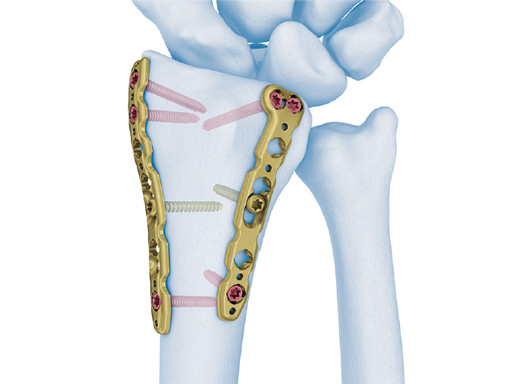

The 2.4 mm VA-LCP dorsal distal radius plate adds variable angle technology to the existing double plate concept of the 2.4 mm LCP dorsal distal radius plates. Additionally, new anatomically preshaped plates have been added to the set: one for the radial column in two different lengths, and one for the intermediate column, also in two different lengths and in left and right versions. All plates are highly polished and have rounded edges to minimize the risk of soft-tissue irritation and tendon ruptures.

The recommended operating room technique for a dorsal shearing fracture is to apply the dorsoulnar plate first, fixed only by a cortex screw in the oblong combination hole. After, the dorsoradial plate is applied in the same way. The locking screws are then inserted in the dorsoulnar plate, starting with the most proximal hole. Finally, locking screws are placed in the dorsoradial plate in the same order. The VA instrumentation allows repositioning of nonoptimally placed screws.